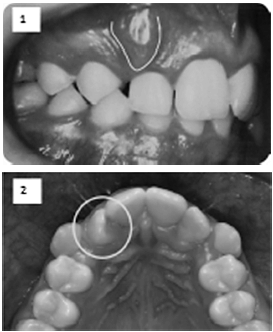

Um sistema de classificação das maloclusões visa agrupar casos semelhantes para facilitar a comunicação entre os profissionais e orientar o plano de tratamento. Conforme a classificação proposta por Lischer (1911), marque a alternativa correta quanto as situações clínicas a seguir, considerando o dente marcado nas imagens: